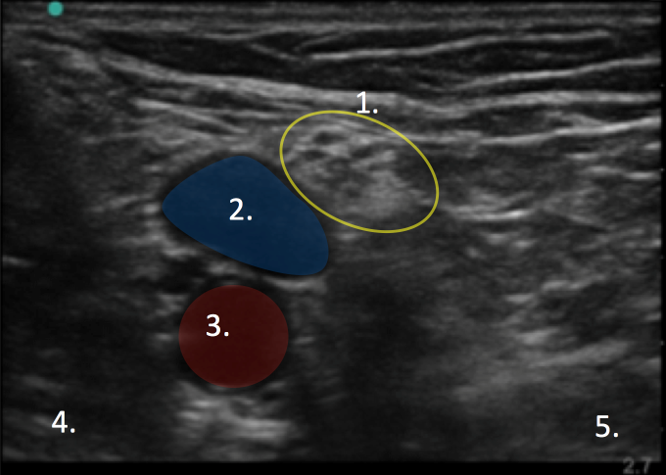

Popliteal Scanning Technique 1 Image

Tibial Nerve

Popliteal Vein

Popliteal Artery

Lateral

Medial